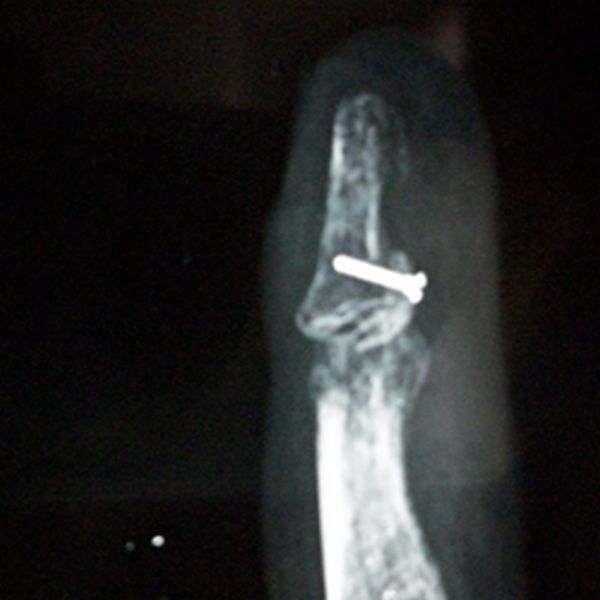

3. Namaste Program (Reconstructive Hand Surgery):

Getting both hands to work to serve the society. This encompasses the surgeries for the correction of acrodactyly, syndactyly, macrodactyly, club hand, claw hand, burn contracture release to name a few.